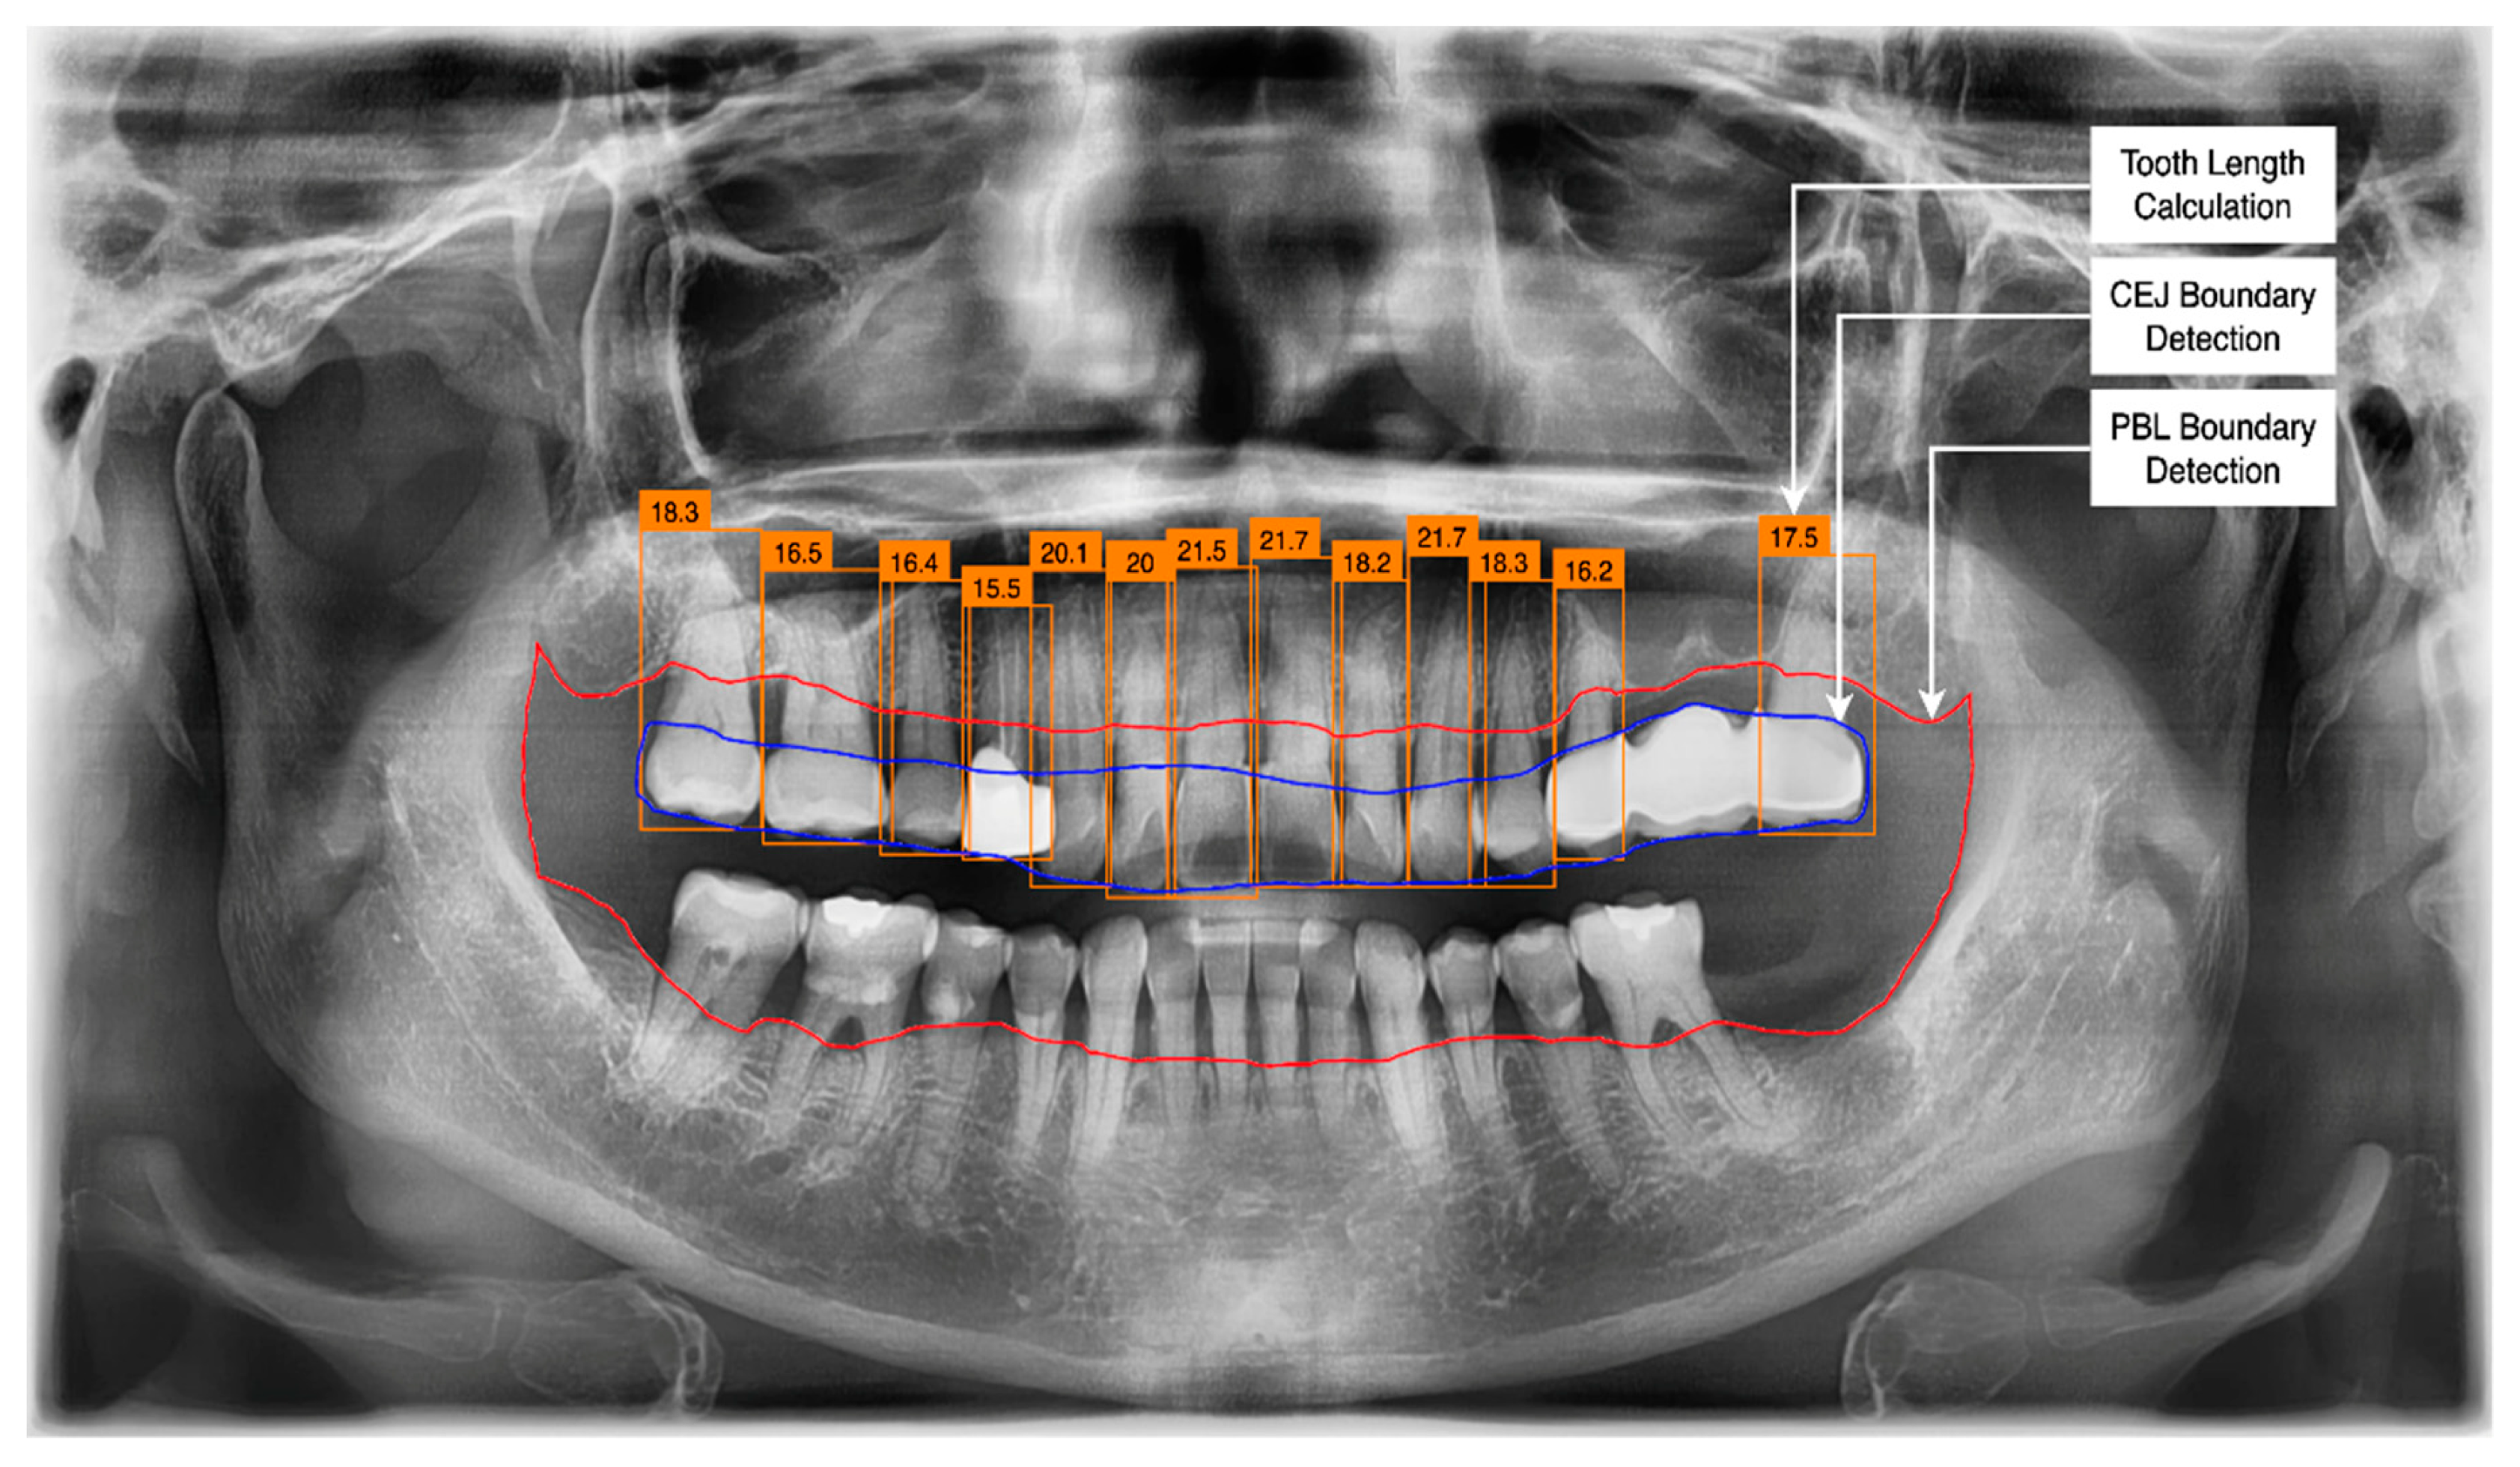

3.2. PBL and CEJ Boundary Detection through U-Net

3.4. Determination of Tooth Stage through U-Net and YOLOv5 Integration